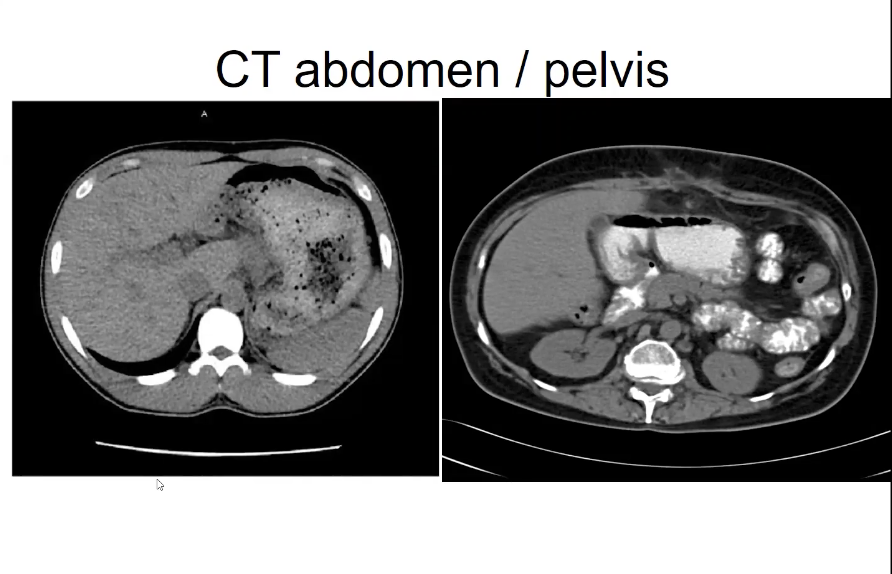

Different phase of contrast